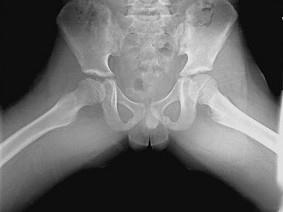

问题 男,8岁,右髋疼痛,活动受限,请结合图像,选出最可能的诊断 ( )

选项 A、退行性骨关节病 B、骨纤维异常增殖症 C、髋关节结核 D、剥脱性骨软骨炎 E、股骨头骨骺缺血坏死

答案 E